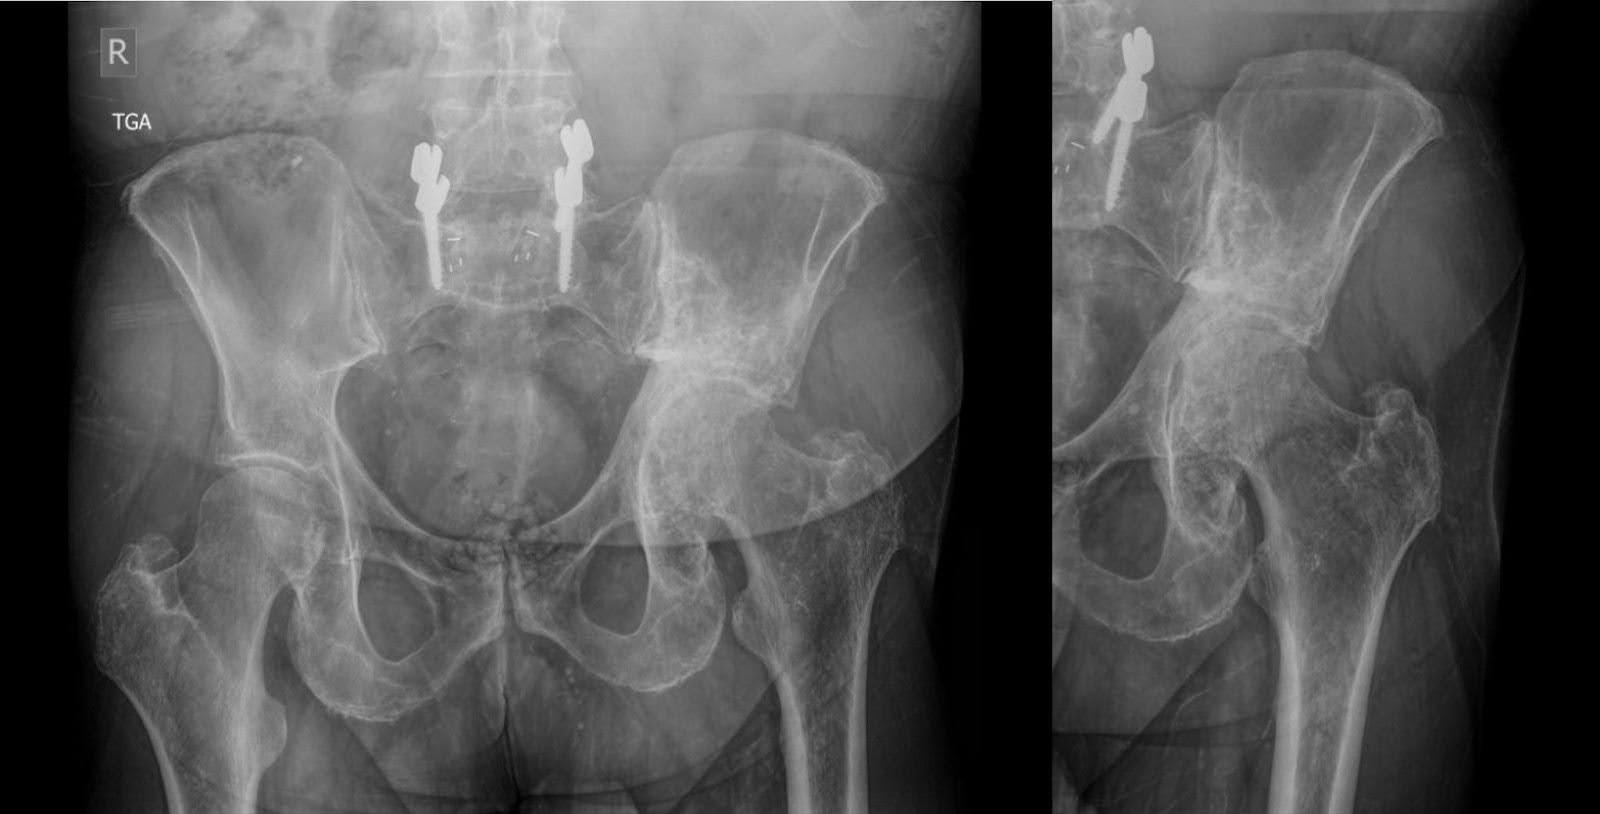

Na apresentação, a radiografia da pelve demonstrou perda de espaço articular do quadril esquerdo, osteófitos, cistos subcondrais e migração proximal do fêmur com alterações da articulação sacroilíaca. Erosão superior leve do acetábulo acompanhada de esclerose atribuída ao linfoma. Alterações degenerativas na articulação sacroilíaca e na sínfise púbica também estavam presentes. Além disso, a fixação transpedicular na junção lombossacral com marcadores de enxerto intersomático decorrentes de cirurgia de fusão lombar realizada oito anos antes para doença degenerativa do disco lombar.

As radiografias subsequentes, realizadas três meses antes da cirurgia, não revelaram nenhuma alteração substantiva na aparência de lesões escleróticas e líticas mistas na hemipelve esquerda, de acordo com o linfoma tratado. Isso foi acompanhado por remodelamento acetabular e migração cranial do fêmur proximal, com alterações degenerativas na articulação do quadril esquerdo (Figura 1). Os achados da tomografia computadorizada (TC) alinharam-se aos radiografados, confirmando a patologia observada (Figura 2).

Figura 1. Radiografias anteroposteriores (AP) da pelve três meses antes da cirurgia. Lesão principalmente esclerótica da hemipelve esquerda, consistente com linfoma tratado. Alterações estruturais do acetábulo com remodelação e migração superior do fêmur proximal.